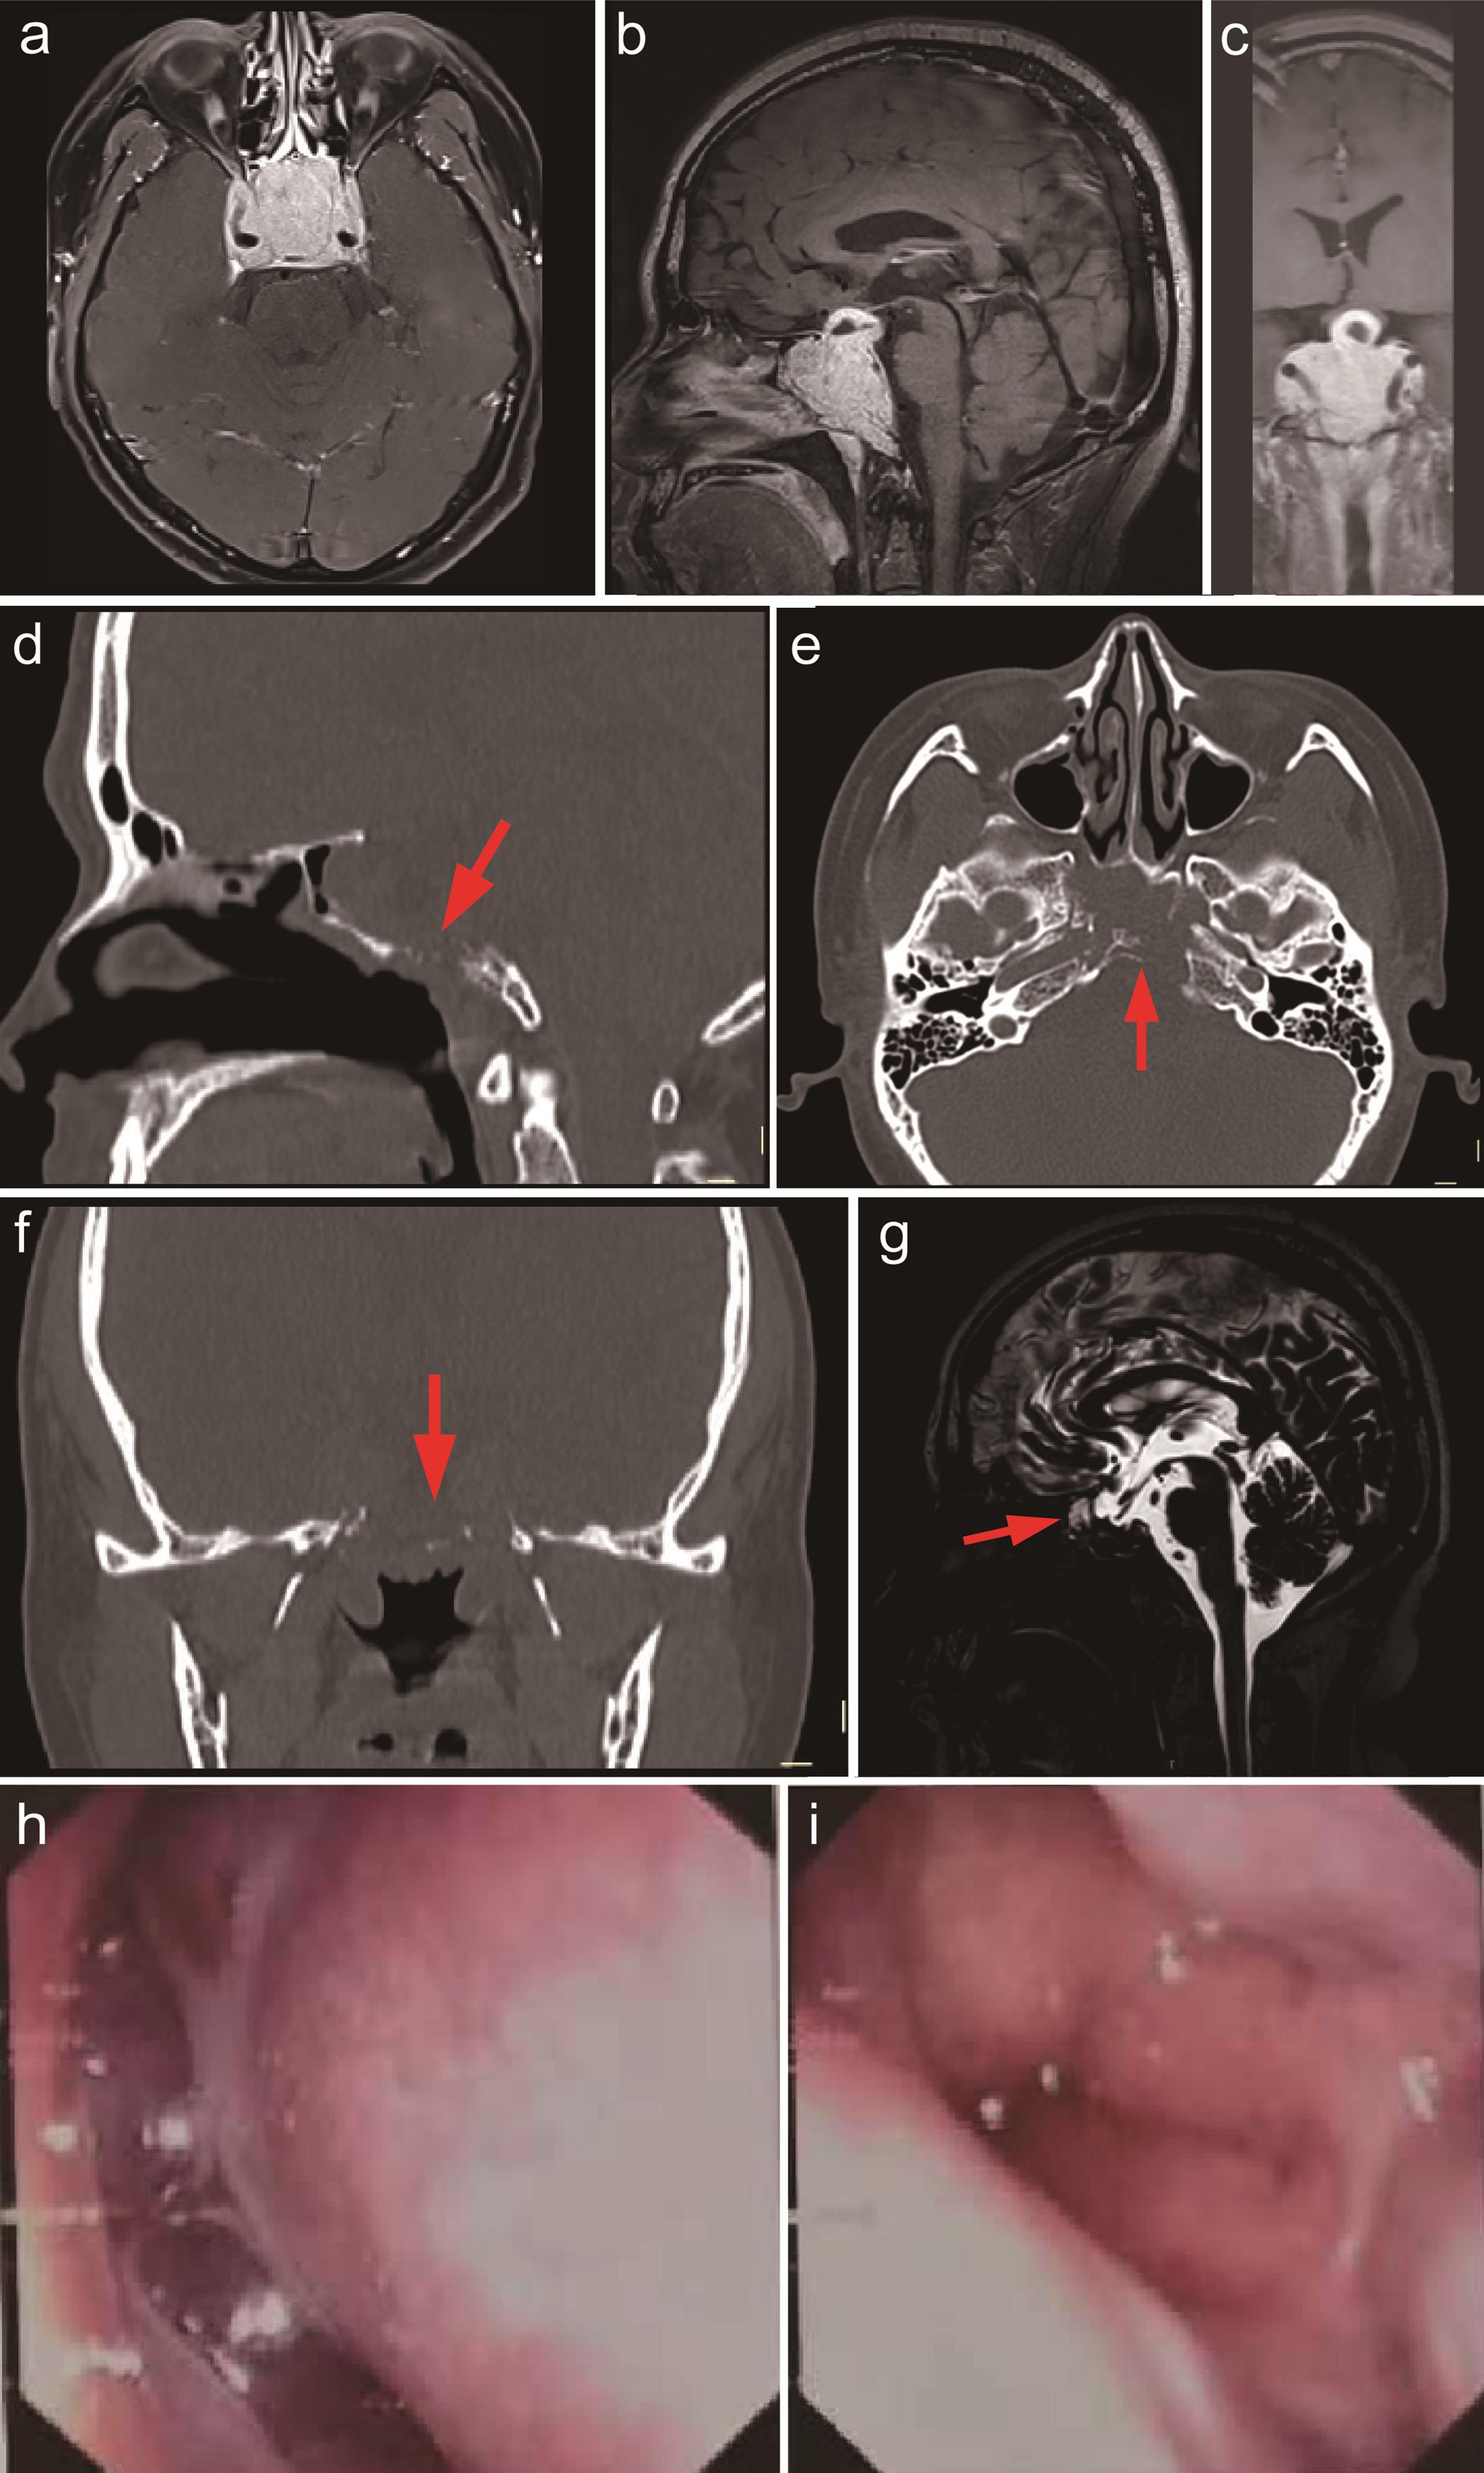

Upon admission, a specialized neurological examination revealed no significant abnormal signs. Further investigations were then performed. Paranasal sinus CT with 3D reconstruction showed a soft tissue density lesion in the sphenoid sinus and sellar region, accompanied by destruction of the clivus, sellar floor, and sphenoid sinus walls (Fig. 2). Pituitary contrast-enhanced magnetic resonance imaging (MRI) (performed on a 3.0-T scanner, including sagittal and coronal T1- and T2-weighted sequences before and after gadolinium administration) revealed a large mass (47×39×44 mm) in the sphenoid-sellar region with marked enhancement. The lesion encased both cavernous sinuses and segments C4–6 of the internal carotid arteries, extended superiorly to involve the adenohypophysis, displaced the pituitary stalk, and elevated the optic chiasm (Fig. 2). Endocrine evaluation demonstrated a prolactin level > 2,000 ng/mL, with low testosterone (1.27 ng/mL) and estradiol (10.11 ng/mL) levels.

Preoperative imaging and endoscopic findings.

Fig. 2  Preoperative imaging and endoscopic findings.

MRI shows a mass (approx. 47×39×44 mm) with marked enhancement in the sphenoid sinus and sellar region. The lesion elevates and displaces the pituitary stalk to the right, pushes the optic chiasm superiorly, and encases both bilateral cavernous sinuses along with segments C4–6 of the internal carotid arteries (a, b, c). CT reveals bony destruction of the clivus, sellar floor, and sphenoid sinus walls (d, e, f, red arrows). CSF hydrography demonstrates a small patch of high signal intensity in the left sphenoid sinus, suggestive of communication with the suprasellar cistern, which confirms that CSF rhinorrhea has led to intracranial infection (g red arrow). Nasal endoscopy shows copious secretions in the left olfactory cleft and pulsatile discharge from the left sphenoid sinus ostium (h, i). CSF, cerebrospinal fluid; CT, computed tomography; MRI, magnetic resonance imaging.

One month after starting bromocriptine, follow-up MRI demonstrated substantial tumor regression, confirming responsiveness to medical therapy. Nevertheless, the patient developed clear nasal discharge consistent with cerebrospinal fluid (CSF) rhinorrhea. Endoscopic examination identified leakage from the left olfactory cleft and sphenoid sinus ostium; imaging confirmed CSF flow (Fig. 2). Shortly thereafter, the patient developed fever (38.9°C) and meningeal irritation signs, consistent with intracranial infection. He received meropenem and lumbar CSF drainage, which yielded clear, colorless fluid. Analysis of the CSF revealed a white blood cell count of 1/µL, a protein level of 0.34 g/L, and a glucose level of 5.06 mmol/L. Cultures were negative. Following infection control, he underwent endoscopic transsphenoidal tumor resection and CSF leak repair on December 31, 2024.